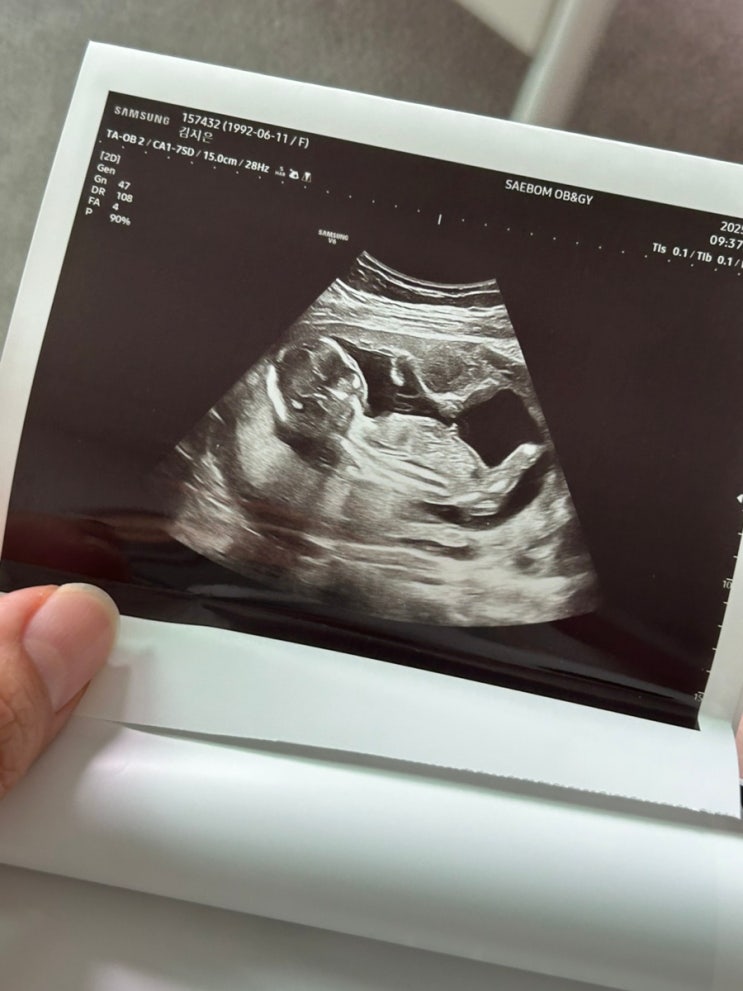

(16주~19주) 성별,장꾸맘 각도법후기,입덧,압박스타킹,다리부종,변비,우울감(+자존감)

16주 16주가 되면 제일 고대하던 성별을 알수 있잖아요~? 이전 포스팅을 보신 분이라면 아시겠지만, 저는 ...